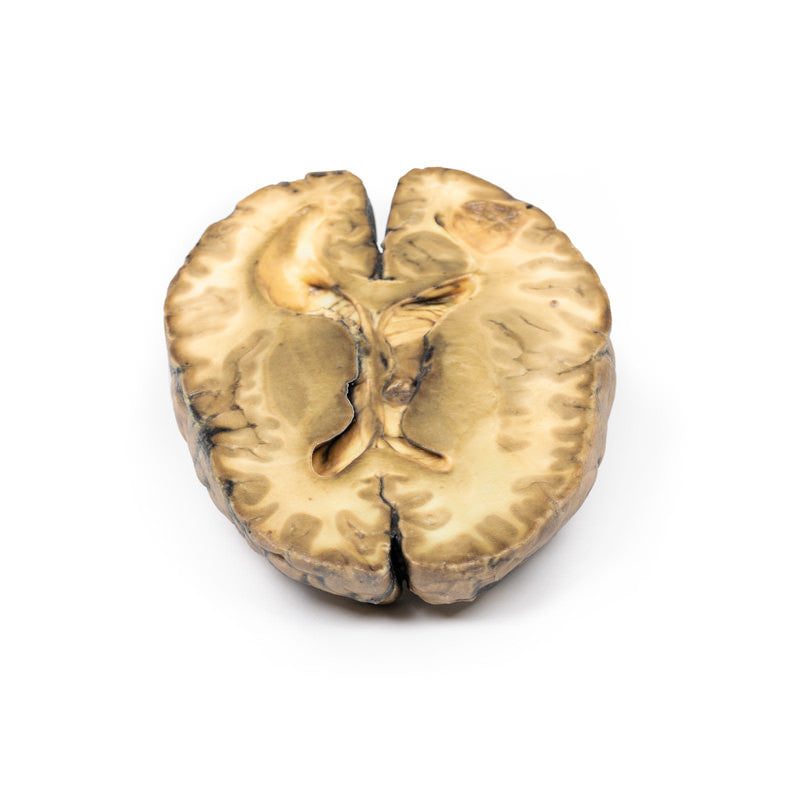

The specimen is the cerebrum sliced horizontally. On the superior view, the right hemisphere is clearly enlarged, particularly in the parietal region where the gyrae are widened and 3 cystic tumours are evident. The largest, 5 cm in diameter, is in the right parietal region. A smaller tumour, 2 x 1.5 cm in diameter, is seen close to the posterior margin of the largest tumour. A third one, 1.5 cm in diameter, is present in the left parietal region. The tumours have mainly involved white matter. The wall of each lesion is composed of shaggy friable greyish tissue. At necropsy, there was ulceration of the largest tumour into the right lateral ventricle (seen more clearly when the inferior surface is examined). Sub-falcine herniation was also seen, as is displacement of the basal ganglia and internal capsule. Histological examination revealed metastatic carcinoma in the viable areas. Other metastases were found in the liver and bone. Histology of a liver metastasis was consistent with origin from a primary carcinoma of breast.